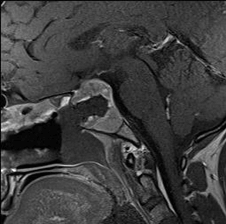

- Intra-operative coronal and sagittal T1W (Figure 2) contrast enhanced sequences show no residual enhancing tumour in the post operative bed (Figure 3).

Figure 2

Figure 3